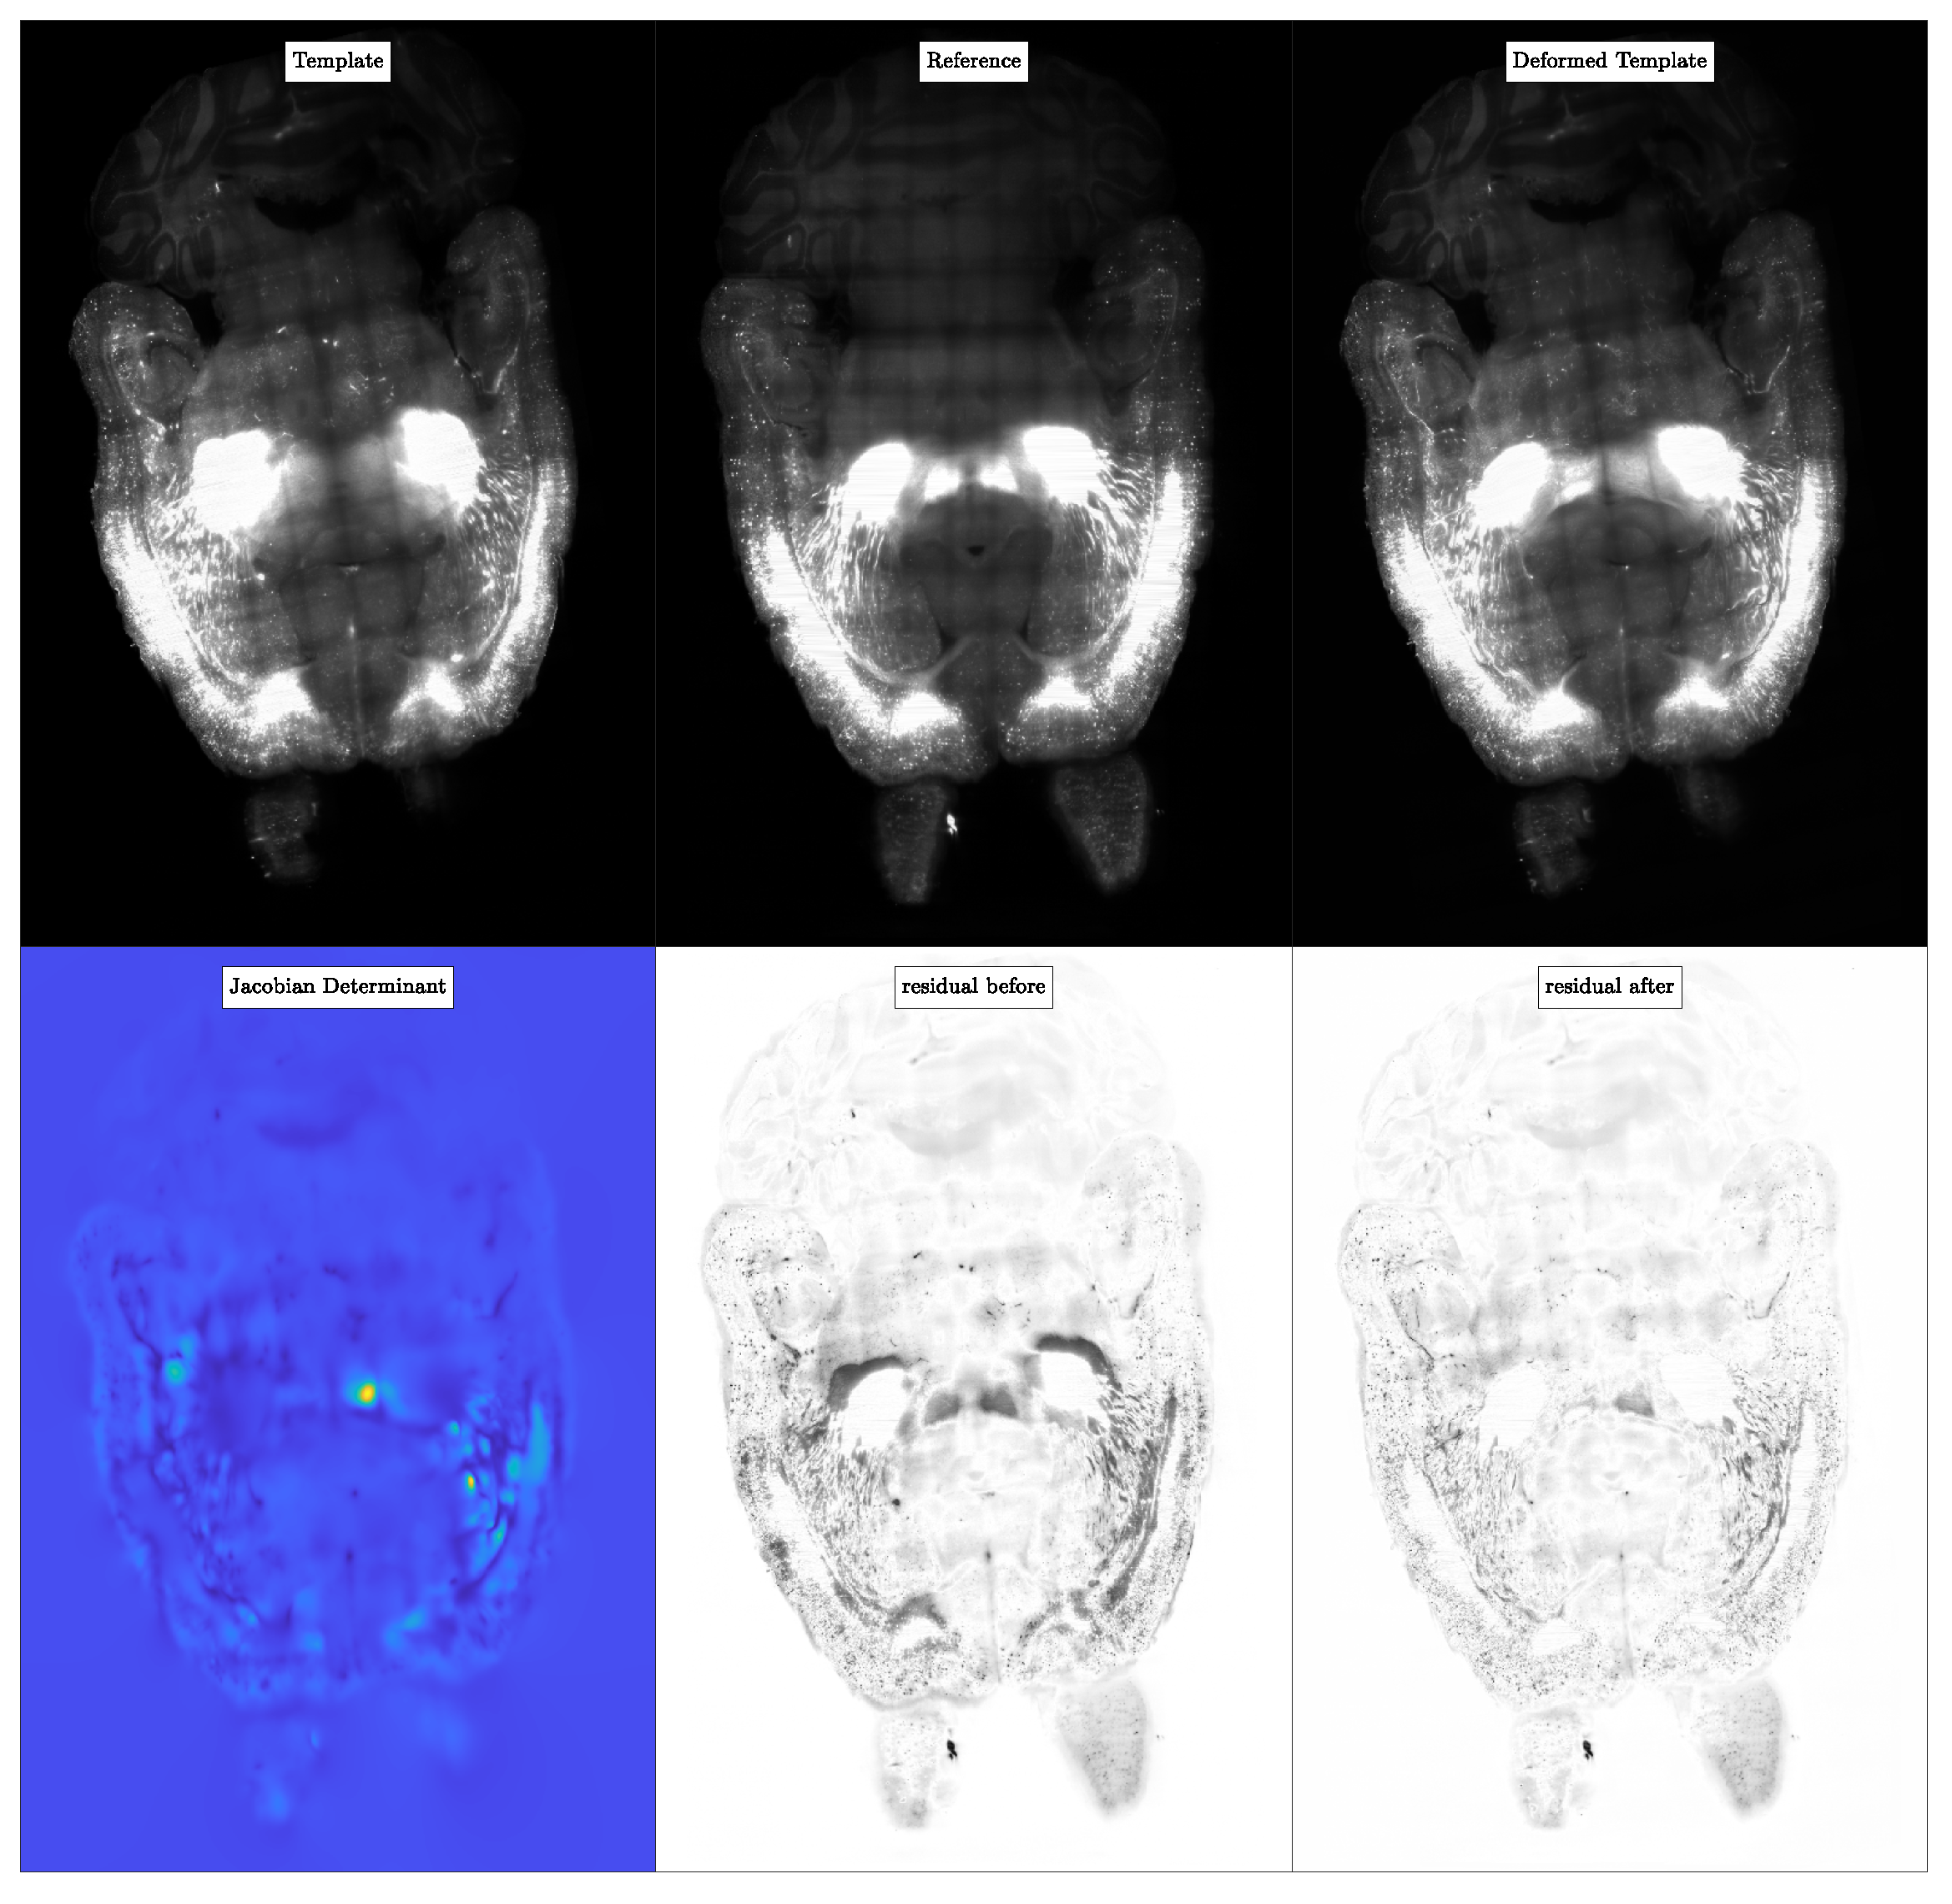

5.5. Experiment 3: Registration of Mouse Brain CLARITY Images

5.5.1. Dataset

5.5.2. Procedure

5.5.3. Results

5.5.4. Observations